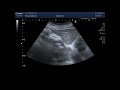

ОПУХОЛЬ У МОЕЙ КОШКИ /ЛЕЧИТЬ ИЛИ НЕ МУЧИТЬ ЖИВОТНОЕ 😪